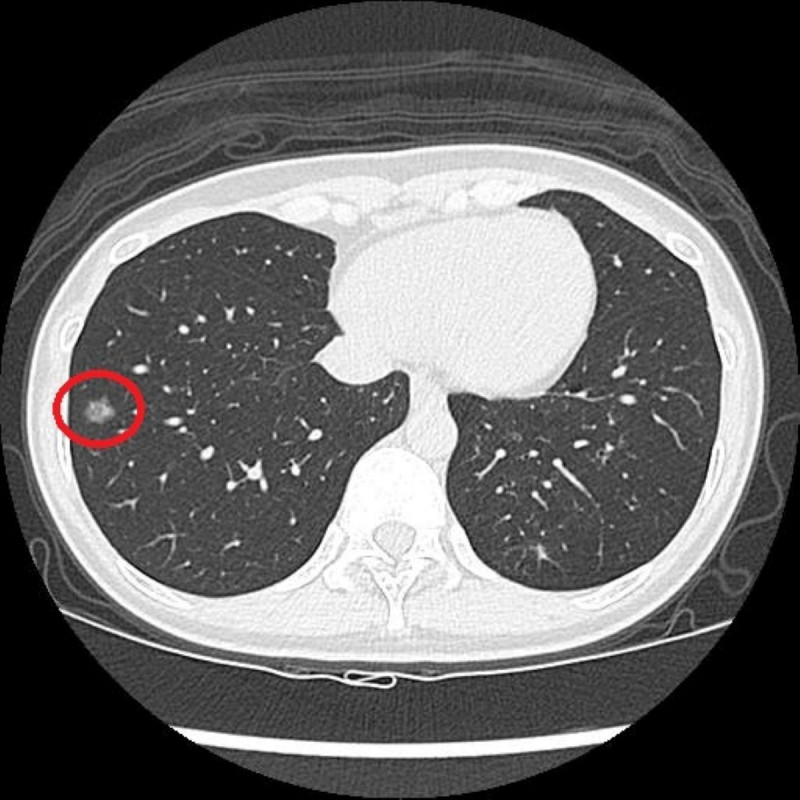

早期肺癌難察覺 國健署補助老菸槍2年1次公費LDCT揪出病灶

原本長期吸菸的41歲陳小姐,2年前在醫療團隊協助下戒菸,因符合國民健康署兩年一次公費「低劑量電腦斷層(LDCT)」篩檢條件,她接受檢查發現右肺有一顆約1.2公分的毛玻璃結...…